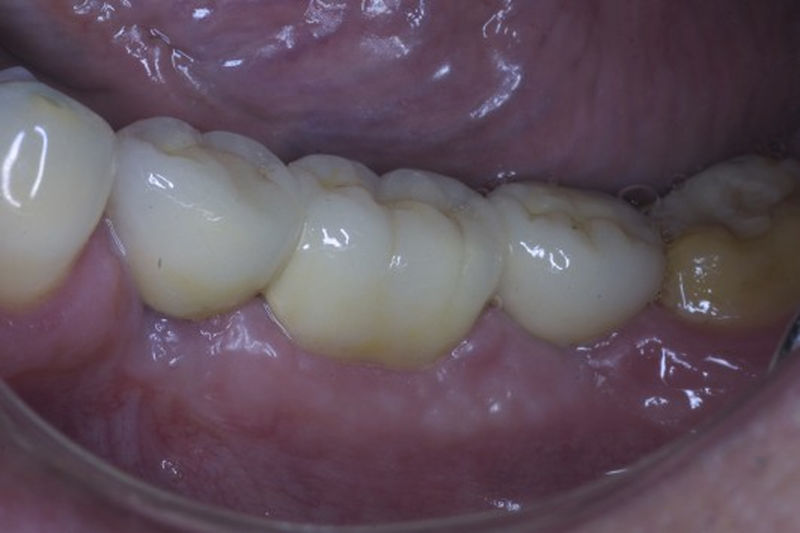

Restauraciones fabricadas en el laboratorio con materiales estéticos, los cuales cubren de manera parcial dientes posteriores. Se utilizan primariamente para restaurar dientes con caries, fracturas y/o defectos amplios. Para poder enviar el caso al laboratorio se toman impresiones utilizando materiales de impresión o técnicas modernas digitales.

Restauraciones fabricadas en el laboratorio con materiales estéticos, los cuales cubren de manera total dientes anteriores y posteriores. Se utilizan primariamente para restaurar dientes con caries, fracturas y/o defectos amplios, así como soportes de puentes. Para poder enviar el caso al laboratorio se toman impresiones utilizando materiales de impresión o técnicas modernas digitales.

Restauraciones fabricadas en el laboratorio con materiales estéticos, los cuales se usan para reemplazar dientes ausentes usando coronas como soporte. Para poder enviar el caso al laboratorio se toman impresiones utilizando materiales de impresión o técnicas modernas digitales.